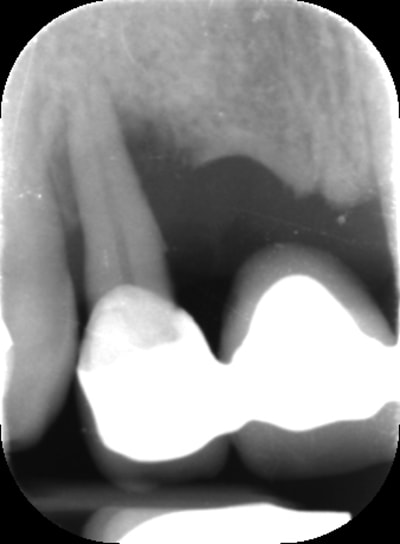

Patiente de 30 ans suite à parodontite a perdu 11-12 avec grosse perte osseuse.

J'ai suffisamment d'os pour prévoir la pose implantaire sans greffe mais esthétiquement je pense que cela va être moche car la ligne du sourire me semble bien haute.

si tu implantes comme ça, on est bien d'accord que ça va être moche.

que comptes tu faire de la 21? as tu une rétro?

il y a un truc qui me chiffonne, tu dis que cette patiente de 30 ans, a perdu ses deux ans suite a une parodontite?, mais alors vraiment très très localisée, car je ne vois aucun problème ailleurs

Bon voila le scann de 11-12 (pas 21-22 comme noté)

C'est vrai que j'ai à mort d'os en épaisseur.

Le manque est surtout en hauteur.